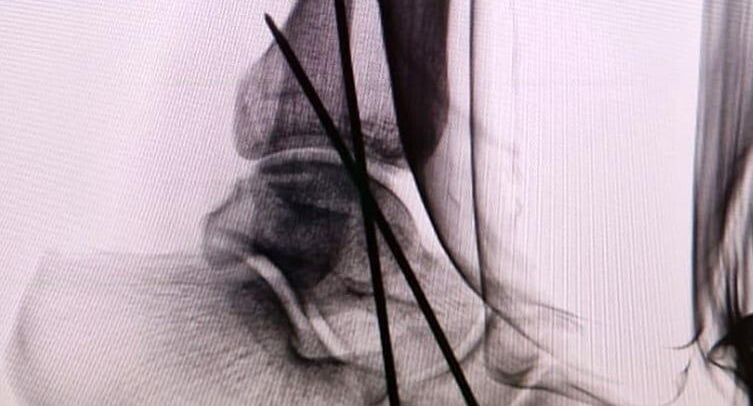

рентген голеностопного сустава после установки спиц / пресс-служба Долгопрудненской больницы

Специалисты провели исследования и выявили у пациента перелом голеностопного сустава и серьезные повреждения четвертого позвонка поясничного отдела, вследствие чего нервные окончания позвоночного столба оказались пережаты.

Пострадавшего перевели в операционную, дали наркоз, после чего травматолог-ортопед Владимир Рублев зафиксировал поврежденный голеностопный сустав.